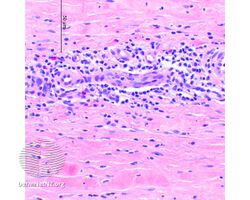

Eosinophilic fasciitis (DermNet NZ dermal-infiltrative-eos-fasc).jpg

Eosinophilic fasciitis

Eosinophilic fasciitis (/ˌəˌsɪnəˈfɪlɪk ˌfæʃiˈtɪs, ˌ-, -ˌfæsi-/[2][3]), also known as Shulman's syndrome,[4] is an inflammatory disease that affects the fascia, other connective tissues, surrounding muscles, blood vessels and nerves. Unlike other forms of fasciitis, eosinophilic fasciitis is typically self-limited and confined to the arms and legs, although it can require treatment with corticosteroids, and some cases are associated with aplastic anemia.[5]

The key to diagnosis is the observation of skin changes in combination with eosinophilia, but the most accurate test is a biopsy of skin, fascia, and muscle.[citation needed]